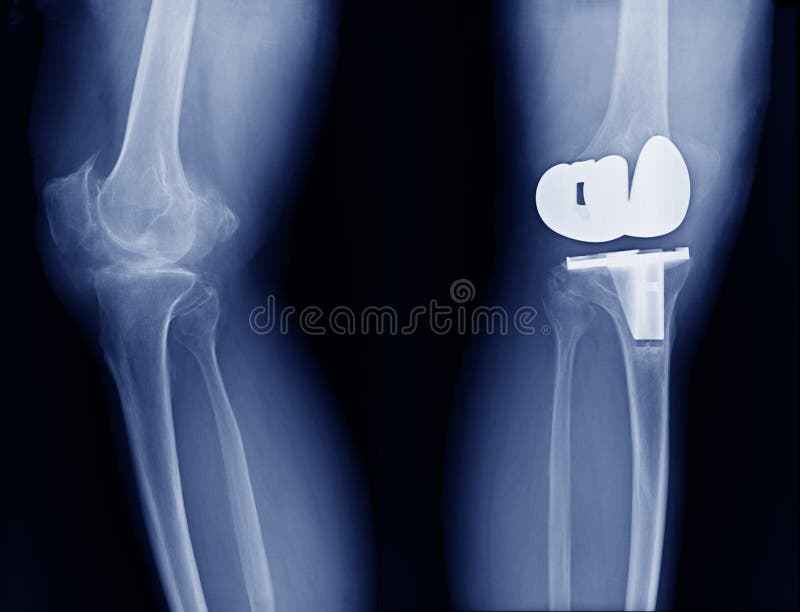

Radiologiczna wizerunku przedstawienia przełamu noga i przedramię. Radiologiczna wizerunku przedstawienia przełamu kość noga i przełamu dyszel ulnar przedramię